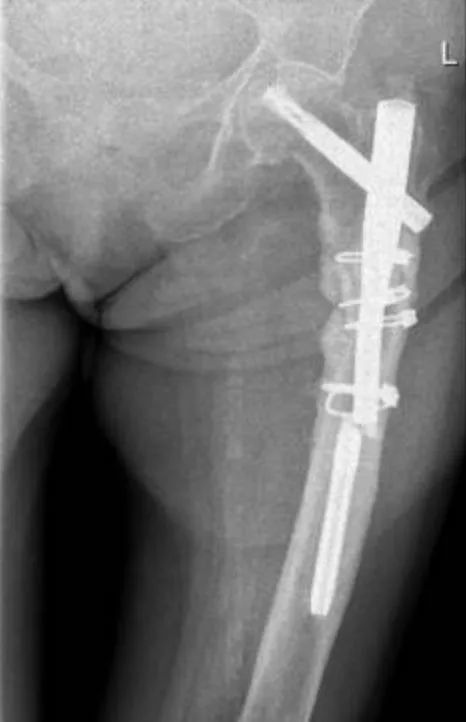

Боль в области большого вертела относительно распространена после антероградного интрамедуллярного введения гвоздей, но ее точная частота не была определена количественно, и эта боль часто не вызвана выпячиванием хвостика гвоздя.Боль в передней части бедра может быть вызвана попаданием кончика интрамедуллярного стержня в переднюю часть коры бедренной кости.В литературе сообщалось, что удаление бедренного интрамедуллярного стержня уменьшает болевые симптомы, хотя в некоторых случаях источник боли не был идентифицирован.

Бедренный интрамедуллярный стержень: многообещающее решение при переломах бедренной кости

Обратный бедренный интрамедуллярный стержень: многообещающий подход при переломах бедренной кости